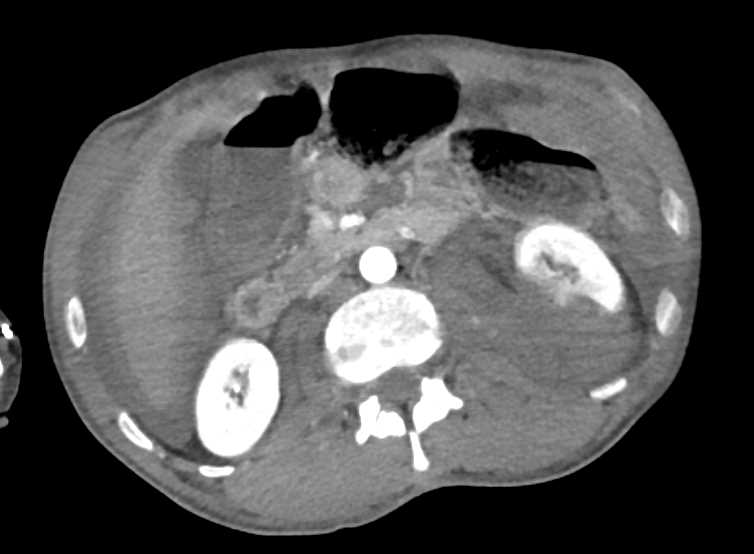

Lipoma in the Transverse Colon